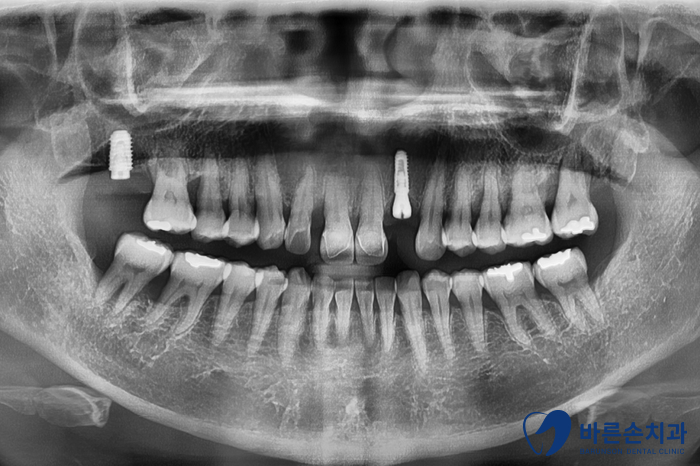

이미 상실되어 있는 어금니와 함께 앞니 임플란트를 가지런히 심었습니다.

앞니 임플란트는 자주 보이는 부분이기에,

잇몸이 내려가지 않도록 식립하는게 관건입니다.

잇몸이 많이 내려가면, 심미적으로 좋지 않거든요.

2개월 뒤 임플란트와 뼈가 단단히 붙어

보철 제작에 들어갑니다.